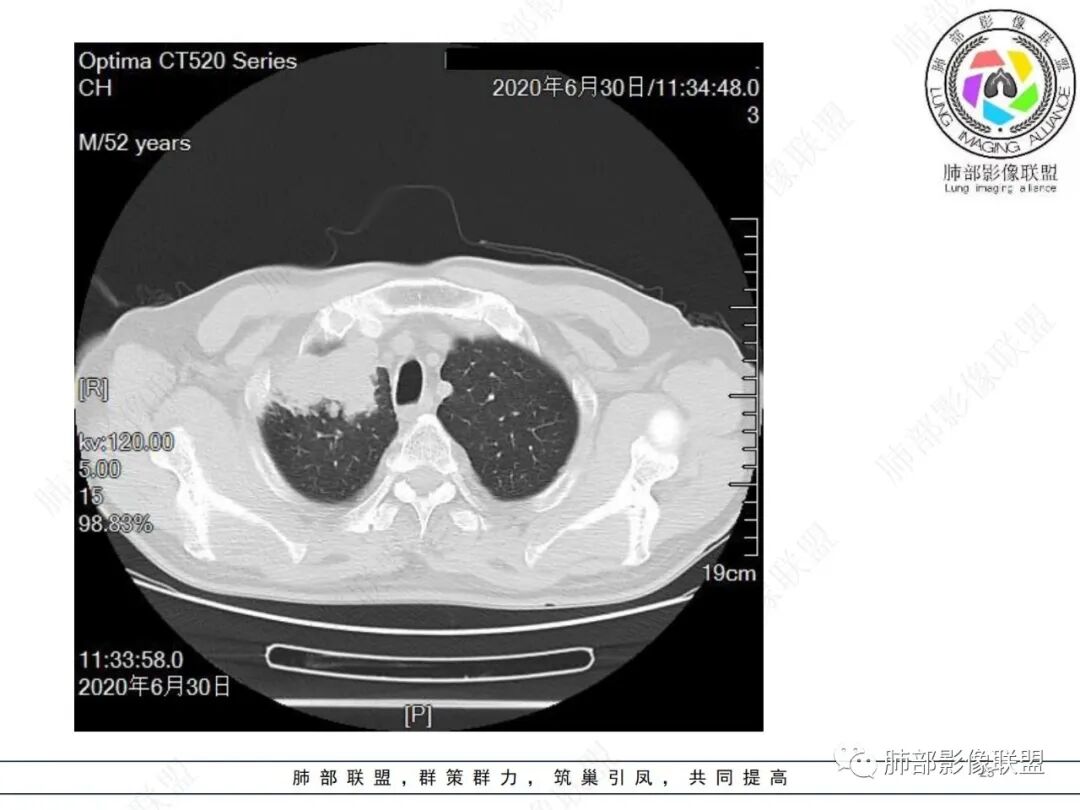

中年男性,有长期吸烟史,右肺上叶不规则肿块,边缘膨隆有分叶,支气管截断,不均匀强化,内有多灶性坏死,癌胚抗原升高,考虑肺癌可能性大,鳞癌可能。鉴别腺癌。

右肺上叶不规则形软组织密度肿块影,边缘见分叶,毛刺,病灶呈宽基底与胸膜相连,病灶内见坏死,增强扫描呈不均匀性强化,右肺上叶支气管截断,纵隔内见肿大淋巴结,肿瘤标志物增高,考虑鳞癌可能,鉴别小细胞癌,腺癌。

右肺上叶不规则肿块,分叶、毛刺,上叶支气管截断,断端圆钝,不均匀强化,其内空泡及坏死,坏死边界不清,考虑腺癌或腺鳞癌,鉴别鳞癌

中年男性,长期吸烟,CT示右肺上叶肿块影,有分叶,毛刺,胸膜牵拉,支气管截断,边缘斑片影,病变内有坏死,强化,淋巴结肿大,首先考虑鳞癌可能性大,鉴别腺鳞癌

除了年龄,吸烟,湖泊样坏死符合鳞癌,其他都不符合,支气管截断,不在肿块中央,远处也没有明显阻塞样改变,更像爬行后截断,肿瘤标志物CEA高得厉害,其他鳞癌标志物并不高。这种坏死,低分化腺癌一样常见,强化远端也有强化,不符合鳞癌,所以我考虑低分化腺癌(伴或不伴有神经内分泌分化)或者肉瘤样癌。

边缘都是强化的肿瘤组织,鳞癌是不会这样的,符合腺癌

不符合鳞癌有四点:1,截断的支气管不在肿块中央,而是外朝内爬行(肿块外缘大于近端)2、支气管截断在前段,前段远端没有阻塞性改变。3、鳞癌是近端强化,远端为阻塞性的不强化粘液栓或明显强化的不张肺组织,这个是中间坏死,周围强化的肿瘤组织。4、肿瘤标志物CEA增高太明显,鳞癌标志物不高。